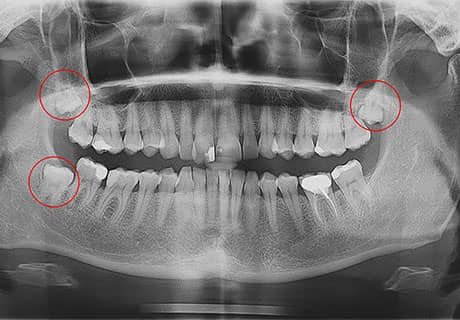

Зубы мудрости выросли не полностью